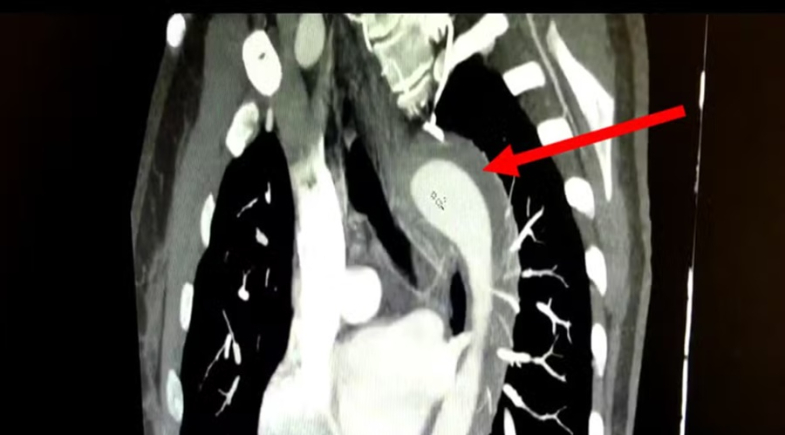

Tomografia de tórax mostra o hematoma intramural da aorta torácica | Foto: American Journal of Case Reports

Exames de imagem confirmaram a presença de um hematoma intramural na aorta, um tipo de sangramento na parede do maior vaso sanguíneo do corpo, considerado uma Síndrome Aórtica Aguda (SAA).